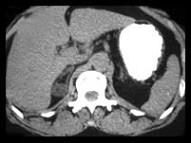

问题 女,35岁,无意中发现血压高,实验室检查:血和尿中醛固酮水平增高,请结合所提供图像,作出诊断 ( )

选项 A、右肾上腺转移瘤 B、右肾上腺囊肿 C、右肾上腺Cushing腺瘤 D、右肾上腺Conn腺瘤 E、右肾上腺增生

答案 D